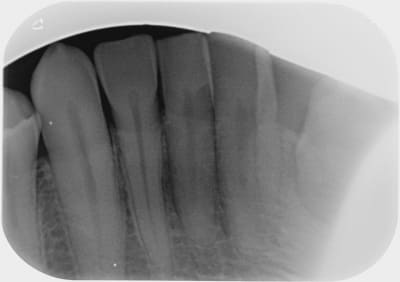

A toutes fins utiles, pour les nouveaux lecteurs, je reposte mes radios.

en ajoutant la 42 également.

J'espère ne pas avoir de problème neuropathique...car j'ai également maintenant une sensibilité sur la 42...cela me l'avait déjà fait..il y a 1 an..et mon patron n'avait rien trouvé.

C'est marrant que la 37 vous interpelle, alors que la 35 (meme la 45!) est beaucoup plus louche, avec un compo juxta pulpaire (mauvais mariage) , et certainement une mortification lente a bas bruit, le truc bien vicelard au diagnostic differentiel difficile.